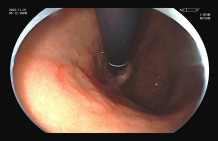

图示:结肠高分化腺癌:镜下呈隆起病变,放大内镜观察:表面结构不规则,微血管扭曲、紊乱、不规则。